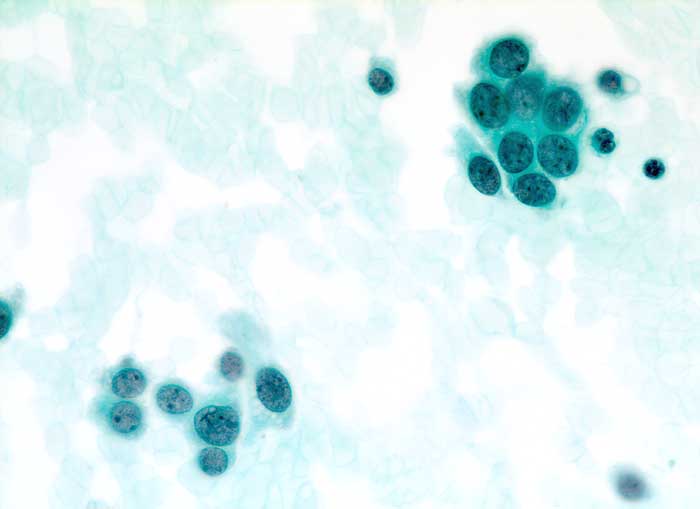

Das duktale Carcinoma in situ (DCIS) wird unterteilt in DCIS mit oder ohne Komedonekrosen. Das DCIS mit Komedonekrosen ist charakterisiert durch offensichtlich maligne Zellen auf nekrotischem Hintergrund. Zytologisch hochdifferenzierte DCIS ohne Komedonekrosen sind monomorpher.

Die individuellen Zellen eines duktalen Carcinoma in situ unterscheiden sich nicht von den Zellen eines invasiven dutkalen Karzinoms. DCIS sind im Gegensatz zum invasiven Karzinom gekennzeichnet durch einen stärkeren Zellzusammenhalt und grössere Uniformität der Verbände mit regelmässigen Abständen der Zellen und geringerem Zellcrowding. Makronukleolen sprechen für ein invasives Karzinom. Kleine Nukleolen hingegen können auch bei benignen Veränderungen auftreten.

Das DCIS zeigt im Gegensatz zur atypischen Hyperplasie eher diskohäsive Verbände und Einzelzellen. Bei der atypischen Hyperplasie sind gutartige Zellelemente beigemischt und die Verbände können irreguläre oder schlitzartige Lumina enthalten.

Unten werden Beispiele von einem zytologisch hochdifferenzierten und einem zytologsich wenig differenzierten DCIS mit Komedonekrosen gezeigt.